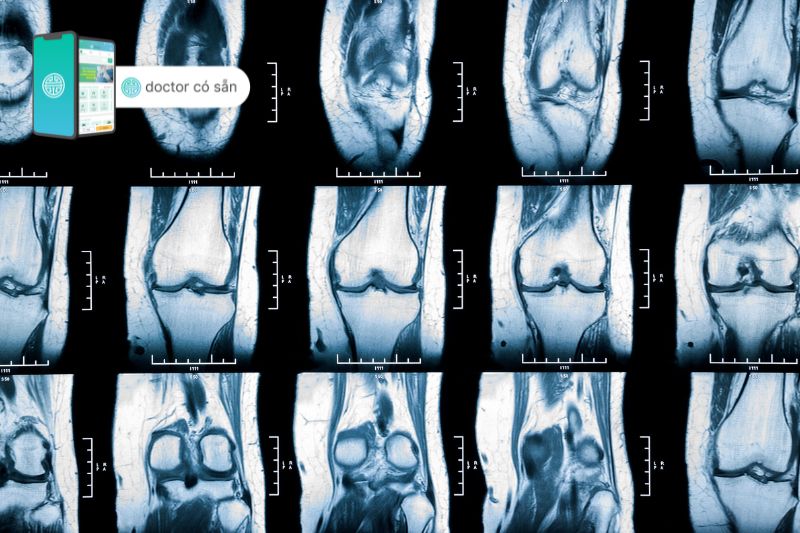

- Chụp cộng hưởng từ (MRI): Điều này có thể cung cấp hình ảnh chi tiết của đầu gối, có thể cho thấy sự tích tụ chất lỏng ở xương đùi hoặc xương đầu gối.